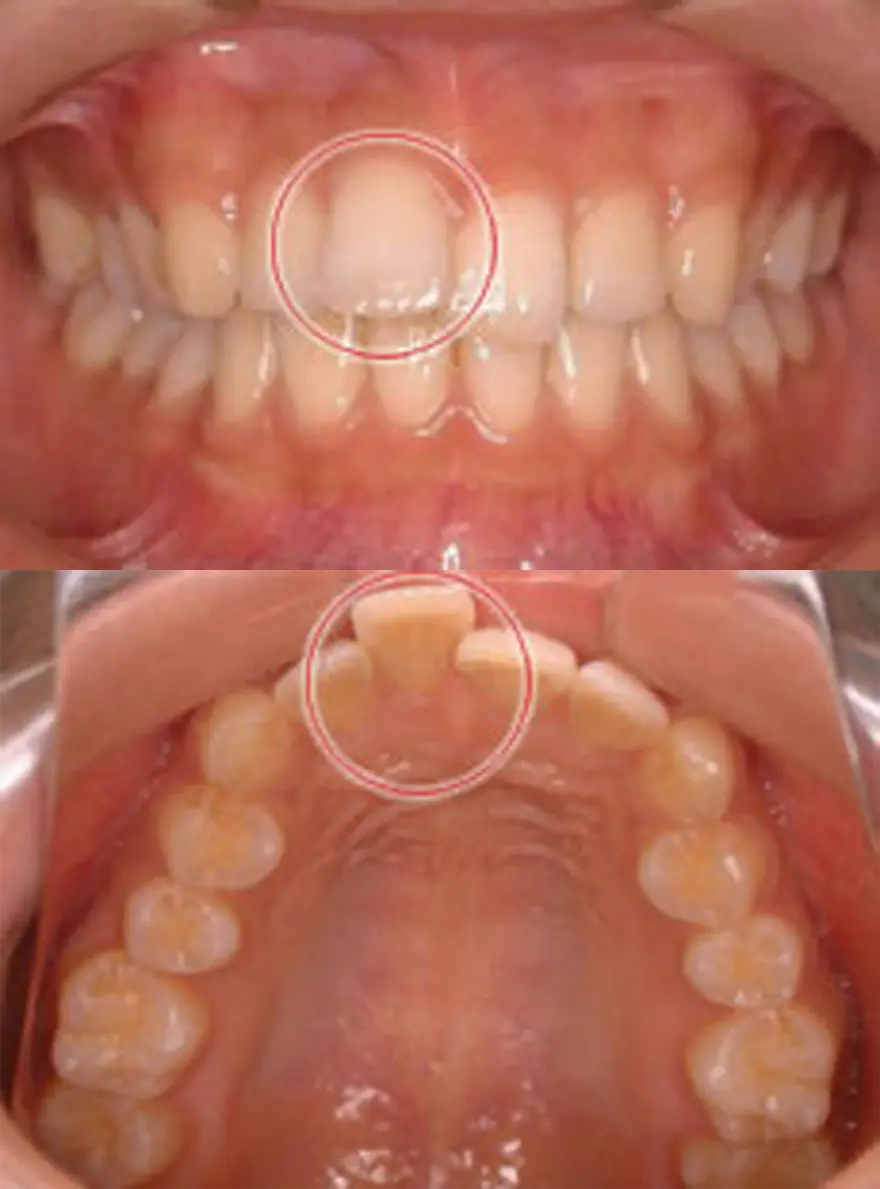

MTM(部分的な矯正)治療例1

飛び出している右の前歯だけ引っ込めたケース

| 患者さまの年齢・性別 | 20代・女性 |

|---|---|

| 治療期間 | 6ヵ月 |

| 治療費(税込) | 352,000円 |

| 主訴 | 右の前歯が前に出ている。 |

| 診断名・主な症状 | 上顎右側中切歯の唇側傾斜をともなう叢生。 |

| 治療に用いた主な装置 | セルフライゲーションブラケット装置(デイモンシステム) |

| 治療内容 |

上顎のみ装置を付け、右の前歯を内側に入れるスペースをつくるため、数本の歯の両端をわずかに削って引っ込めています。歯と歯の間を削る量は決まりがあり、虫歯や歯がしみるなどの原因にならない量を削ります。 |

| 抜歯部位 | 非抜歯 |

| 通院回数・メンテナンス頻度 | 6回 |